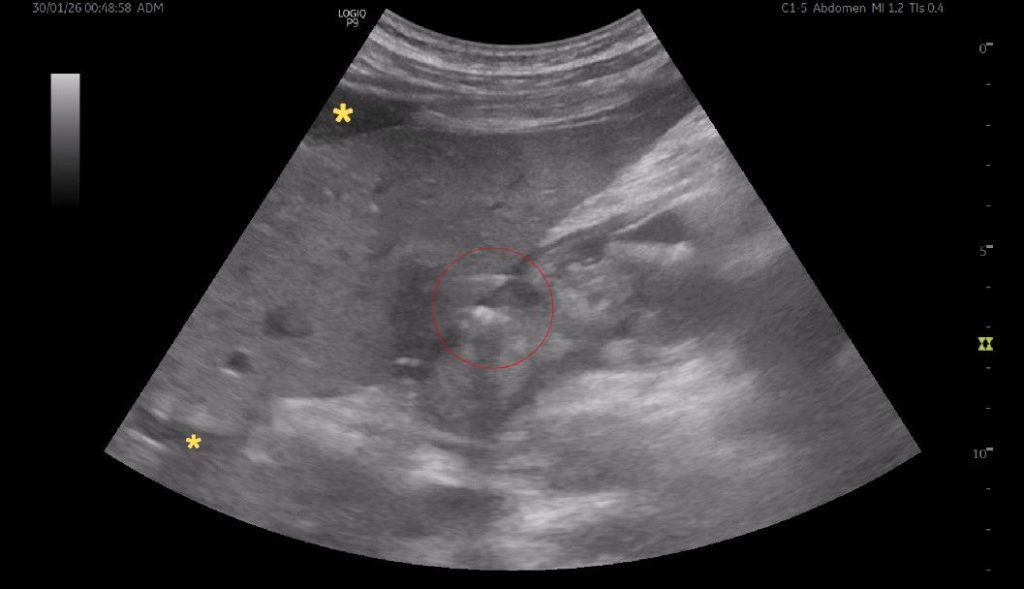

FIGURE 1 and VIDEO 2: Ultrasonography demonstrates the presence of free fluid within the peritoneal recesses, predominantly in the perihepatic and subhepatic regions (yellow asterisks). The fluid appears mildly echogenic, suggestive of inflammatory exudate rather than simple transudate. The duodenal bulb (D1 segment) is thickened and edematous. The area outlined in red demonstrates multiple hyperechoic foci with reverberation artifacts consistent with extraluminal free gas, adjacent to a focal mucosal wall defect. These findings are highly suggestive of a perforated duodenal ulcer.

FIGURE 1 and VIDEO 2: Ultrasonography demonstrates the presence of free fluid within the peritoneal recesses, predominantly in the perihepatic and subhepatic regions (yellow asterisks). The fluid appears mildly echogenic, suggestive of inflammatory exudate rather than simple transudate.

The duodenal bulb (D1 segment) is thickened and edematous. The area outlined in red demonstrates multiple hyperechoic foci with reverberation artifacts consistent with extraluminal free gas, adjacent to a focal mucosal wall defect. These findings are highly suggestive of a perforated duodenal ulcer.